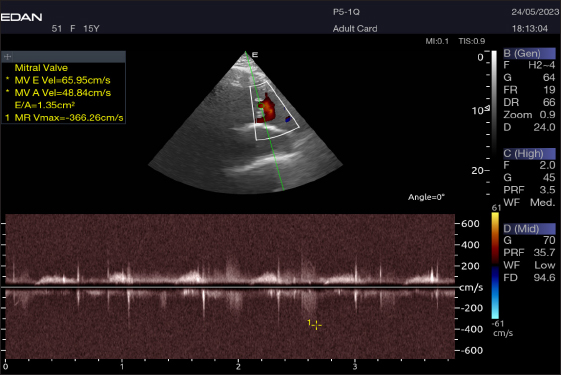

Table 4 provides an overview of pulsed-wave Doppler echocardiographic serial measures in adult racing camels. The pulsed-wave Doppler echocardiographic measurements’ mean values ± standard deviation were recorded for Tv E/A (1.3 ± 0.2 cm2), Mv E/A (1.3 ± 0.2 cm2), Av max (−88.2 ± 25.1 cm/second), and Pv max (−59.2467 ± 17.4 cm/second), as shown in Table 4.

The Mv E/A (Fig. 8), Tv E/A (Fig. 9), and maximum velocity of the aortic valve (Av Vmax) (Fig. 10) were all measured using pulsed-wave Doppler at LPSLAx in all camels. Two cases were observed with mild mitral regurgitation detected through continuous-wave Doppler, but the regurgitation was not considered significant (Fig. 11).

Fig. 8. Left parasternal longitudinal axis of a 16-year-old racing camel showing pulsed wave Doppler over the mitral valve (1=E wave and 2=A wave).